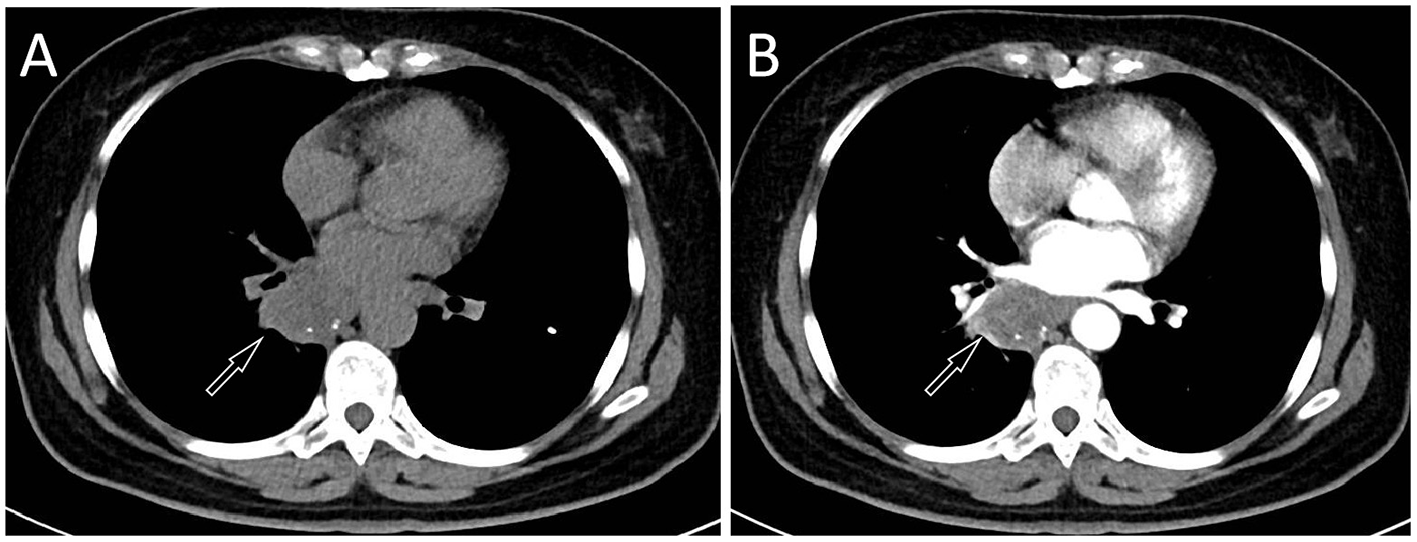

A 57-year-old female patient accidentally discovered a soft tissue mass in her posterior mediastinum during a physical examination in an outside hospital on 11 November 2023. She consciously had no obvious clinical symptoms and was not paid attention to, nor was undergoing any treatment. On 20 April 2024, the patient came to our hospital for medical help due to a cough and chest tightness. The physical examination did not reveal any positive signs. She and her family have denied any history of cancer or major genetic disorders. The serological laboratory test results revealed that the treponema pallidum antibody was positive, while other results, including blood routine, liver and kidney function, and serum tumor markers, were all negative. She had a history of syphilis 15 years ago; the condition resolved completely following treatment, and there are currently no clinical or serological indications of recurrence. She denied any history of tuberculosis, hepatitis, or malignancies. The patient underwent chest computed tomography (CT) examination (Figure 1) on April 24, which revealed a well-defined soft-tissue density mass in the posterior mediastinum with calcification. Contrast-enhanced CT showed a slight enhancement of the mass, suggesting a possible neurogenic tumor. The patient underwent surgical complete resection of the tumor through thoracoscopy under general anesthesia on April 26 after completing the preoperative routine examination. During the operation, the tumor was found to be located between the spine, azygos vein, trachea, and esophagus, with a size of approximately 6 cm × 4.5 cm × 4.0 cm, spindle-shaped, with a complete capsule and no obvious adhesion to surrounding structures. The tumor was gradually separated along its edges using an ultrasonic knife until it was completely removed, and then sent for pathological examination. Hematoxylin–eosin staining (as shown in Figure 2) showed that the excised tumor tissue appeared as a gray–red envelope block with intact capsule, medium texture, and calcified lesions in some areas. No tumor invasion was observed at the resection margin. Immunohistochemistry revealed tumor cells positively expressed vimentin, Cluster of Differentiation 34 (CD34), cytokeratin (CK), and CD56, while they negatively expressed insulinoma-associated protein 1 (INSM1), S100, CD68, and so on. Based on these histopathological findings of the patient, she was diagnosed with PES. After surgery, the patient did not receive further radiotherapy, chemotherapy, or other treatment methods. At 4 months after discharge, a chest CT examination revealed a new soft tissue density nodule at the site of her previous surgery. In order to further evaluate the nature of the nodule and determine the next treatment plan, the patient underwent 18F-FDG PET/CT imaging (as shown in Figure 3) on August 20. The results showed that the above nodule, as shown on CT, showed a significantly increased 18F-fluorodeoxyglucose (18F-FDG) uptake, while no significant hot spots were observed in the rest of the body. These imaging findings suggested the possibility of local recurrence of the tumor, and due to the limitation of the lesion, the surgeon planned to perform a second operation on her. However, the patient refused surgery again. On October 16, the patient returned to the hospital for chest pain and underwent chest CT examination (Figure 4), which showed that the mass was significantly larger than before. Currently, she is receiving a chemotherapy regimen of epirubicin in combination with isocyclophosphamide.

Figure 2

(A) Hematoxylin–eosin staining (magnification, 100 × ) showed diffuse nodular epithelioid cells in tumor tissue, accompanied by necrosis and bleeding. Immunohistochemical results revealed that the tumor cells positively expressed CK (B), vimentin (C), and CD34 (D).